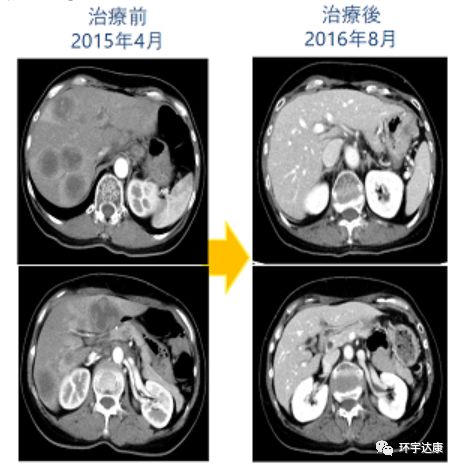

portant; word-wrap: break-word !important; overflow-wrap: break-word !important;">59岁的张女士在2015年4月确诊为IV期肠癌,肝上多发转移,已经没有手术机会。采用XELOX方案化疗+WT1肽抗原树突细胞治疗。

portant; word-wrap: break-word !important; overflow-wrap: break-word !important;">张女士初次回输体内的CTL(细胞毒性T细胞)含量为0.01%,在进行7次树突细胞治疗后,体内的CTL的含量达到0.33%!

portant; word-wrap: break-word !important; overflow-wrap: break-word !important;">更为振奋的是,2016年11月,张女士的CT扫描结果显示病灶全部消失了,病理检测结果也证实了张女士达到了完全缓解状态。